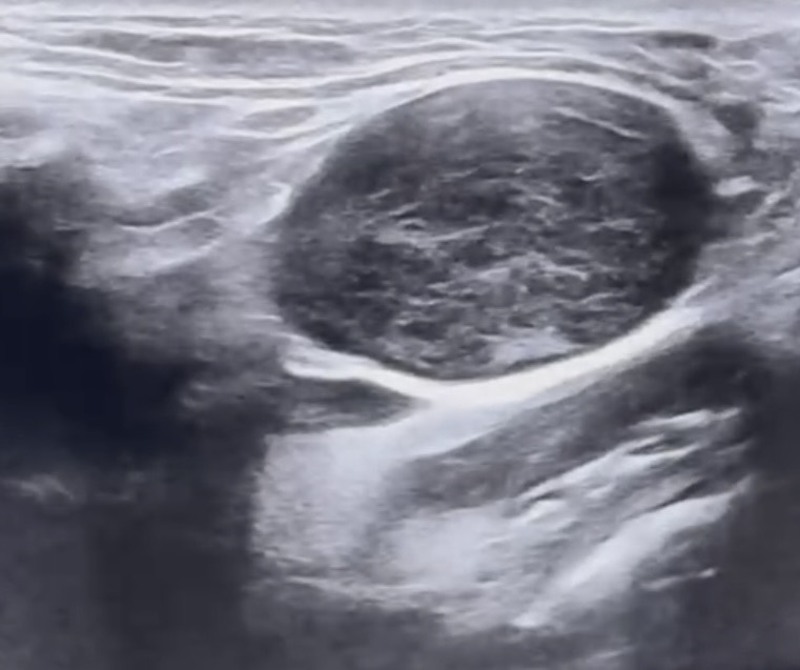

Đặc điểm siêu âm thang xám

- Hình dạng: hình bầu dục trục ngắn/ trục dài > 0.5 (ngoại trừ hạch dưới hàm và tuyến mang tai)

- Độ hồi âm: giảm âm so với cơ lân cận

- Cấu trúc

- Còn rốn hạch

- Bờ đều

- Không có vôi hay hoại tử, hóa nang.

- phù nề mô mềm xung quanh

- Siêu âm:Vùng góc hàm bên trái ghi nhận vài cấu trúc hạch echo kém xen lẫn dải echo dày không đồng nhất, mất rốn, bờ đều kích thước từ 26-32mm, dạng bầu dục, mạch máu phân bố ngoại vi lẫn trung tâm.